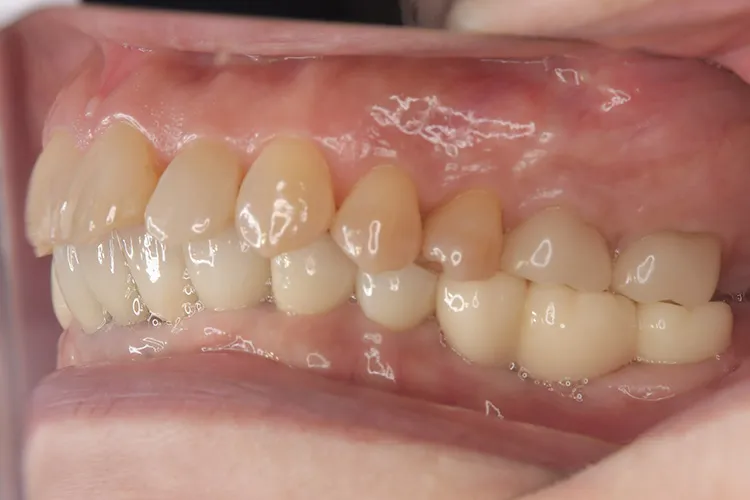

歯ぎしり・食いしばりが強い方の治療ケースです。全体的に歯が擦り減り正面から見て下の歯が見えないほど噛み合わせの高さが失われており、顎関節にも症状がでていました。ヒビが入って保存不可の歯を抜歯しインプラントを計5本埋入し、前歯・臼歯にインプラント土台のブリッジを入れることで噛み合わせの高さを回復しました。古い金属の被せ物もジルコニアでやりかえました。噛み合わせの高さが改善したことで顎関節症状もなくなり快適に過ごされています。歯ぎしりがある方は、夜間のナイトガード装着が必要になります。